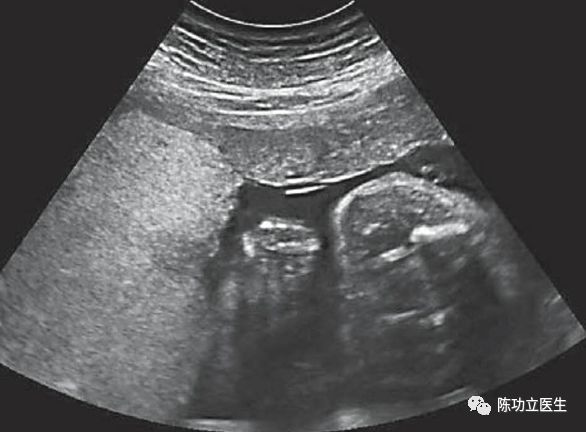

2.射频消融减胎术:对于进展迅速,III期/IV期的TAPS可以选择射频减胎术。

上图来源于网络

3.胎儿镜手术:胎儿镜下SOLOMON手术,因TAPS不合并羊水量异常,手术难度高,且预后不确定,不做常规推荐,仅适用TAPS合并有羊水量异常的病例。